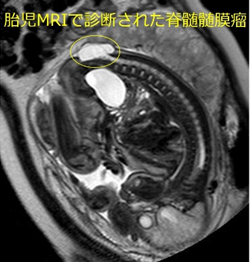

脊髄髄膜瘤は、脊髄がうまく形成されず体表に露出したものです。放置すれば高率に感染をきたすため、生後早期に修復術が必要になります。

脊髄髄膜瘤では約90%と高頻度に水頭症を合併し、通常は生後早期にV-Pシャント術を行います。また、大部分の患者さんで小脳の一部が下方に落ち込んでいるキアリⅡ型奇形がみられますが、このうち約10%で減圧術が必要となります。

脊髄の形成が不十分であるため、程度の差はありますが多くの患者さんで下肢の麻痺や排尿排便障害という後遺症が残ります。脳神経外科だけでなく、整形外科や泌尿器科で診てもらうことも必要になります。リハビリもとても重要です。脊髄髄膜瘤ではいろんな部署のスタッフが協力して長期にわたり子どもたちの治療をすすめていきます。現在では、幼少時に脊髄髄膜瘤の治療を受けた子どもたちがたくさん社会で出て活躍しておられます。